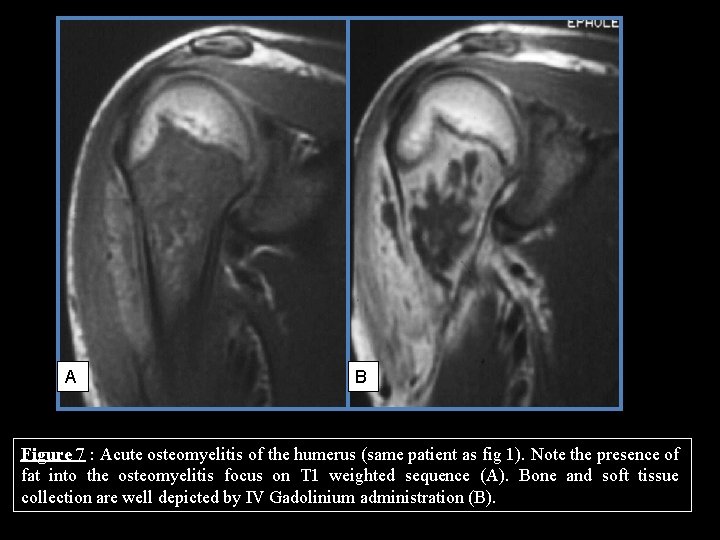

MRI FINDINGS: BONE MARROW EDEMA • Intravenous contrast administration enhances the periphery of bone collections and makes their detection easier (fig. 7) • Bone marrow edema is a sensitive but not specific sign of osteomyelitis. • Optional signs are more specific of this diagnosis – Fat globules – Penumbra – Double line

MRI FINDINGS: FAT GLOBULES • Acute osteomyelitis causes septic necrosis of bone marrow • Fat sediments with pus may resulting in intra or extra-osseous fat-liquid levels • The presence of fat in acute osteomyelitis may result from either the persistence of normal bone marrow surrounded by edema or the presence of linear or globular foci of necrotic bone marrow (fig. 7) • The presence of fat in soft tissues is an indirect sign of cortical disruption (fig. 8)

A B Figure 7 : Acute osteomyelitis of the humerus (same patient as fig 1). Note the presence of fat into the osteomyelitis focus on T 1 weighted sequence (A). Bone and soft tissue collection are well depicted by IV Gadolinium administration (B).